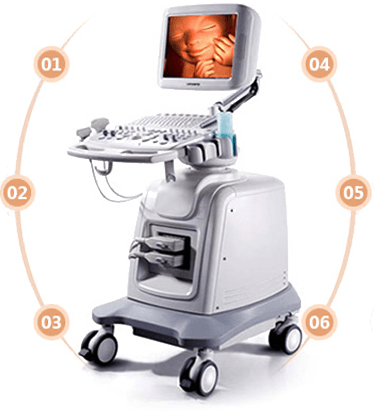

很多孕妈咪疑惑,“听说麦迪逊X8四维彩超跟普通的四维彩超差别很大,可是不知道到底有哪些区别呢?

妈妈们不难看出,麦迪逊X8四维能直观、立体显示人体器官的三维结构形成一边串的动态图像,具有以下优势。

同其它超声诊断过程相比,可以实时的观察人体内部器官的动态运动,检测胎儿先天性缺陷的准确度更高,误诊漏诊现象低。

多方位、多角度的观察宫内胎儿的生长发育情况,为早期诊断胎儿先天性体表畸形和先天性心脏疾病提供准确科学依据。

独特空间复合图像采集及处理能力,快速实时获取完事的图像信息,能为胎儿进行宫内拍照片和动态视频录制,珍藏宝宝宫内的印记。

迈迪逊X8四维彩超采用的是工程设计学原理,不存在射线、光波和电磁波等方面的辐射,对孕妇以及胎儿的健康不会造成影响。

技术优点:

先进的实时四维彩超设备

B、360度立体成像让数据更全面;

C、能呈现更真实、详细的胎儿结构,让胎儿产前排畸更精确;

D、能快速实时自主的获取完整胎儿心脏的容积图像和周期图像信息;

E、不存在射线。光波和电池波等辐射。